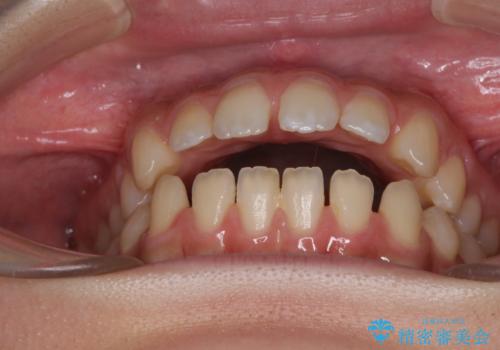

- 上下前歯の隙間と咬み合わない前歯を気にして来院された患者様です。

開咬の治療は、前歯を閉じるように動かすとともに、上下臼歯を圧下(骨内にめり込ませる)させることで進めて行きます。

仕上がりとしては、もう少し上下前歯を接触させたかったのですが、ここまで改善されたことで患者様は大変満足され、治療を終えることとなりました。